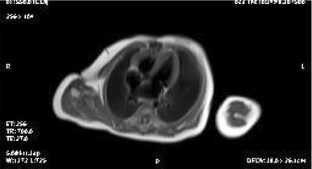

During the fetal-neonatal period, a primary cardiac tumor may be completely asymptomatic and such tumors may be incidentally discovered by echocardiography. A four-hour-old male was diagnosed to have a cardiac tumor by post-natal echocardiography and was observed closely. Surgery was indicated immediately at the 3 week follow-up examination when the tumor was found to have obstructed the right ventricle outflow. The tumor was resected successfully and its histopathology indicated that it was a fibroma. Follow-up echocardiograms and magnetic resonance imaging 5 months postoperatively demonstrated no evidence of any remaining tumor and his RV function was good.

Fig. 1

Fig. 2

Fig. 3

Fig. 4